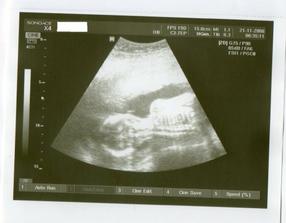

21.11. KO+velký ultrazvuk...........20+1 na velkém UTZ mimi v pořádku,jen se nám nechtělo ukázat.A dr.mě pro jistotu posílá ne genetický UTZ,objednala jsem se do Libereckého Genettu.Tam jedeme 28.11.

Tak jsme po UTZ,miminko se mlelo a krásně hýbalo,vše bylo vidět,vše je v pořádku a hlavně

JE TO KLUK....TAKŽE BUDEME MÍT MATYÁŠKA🙂))))))